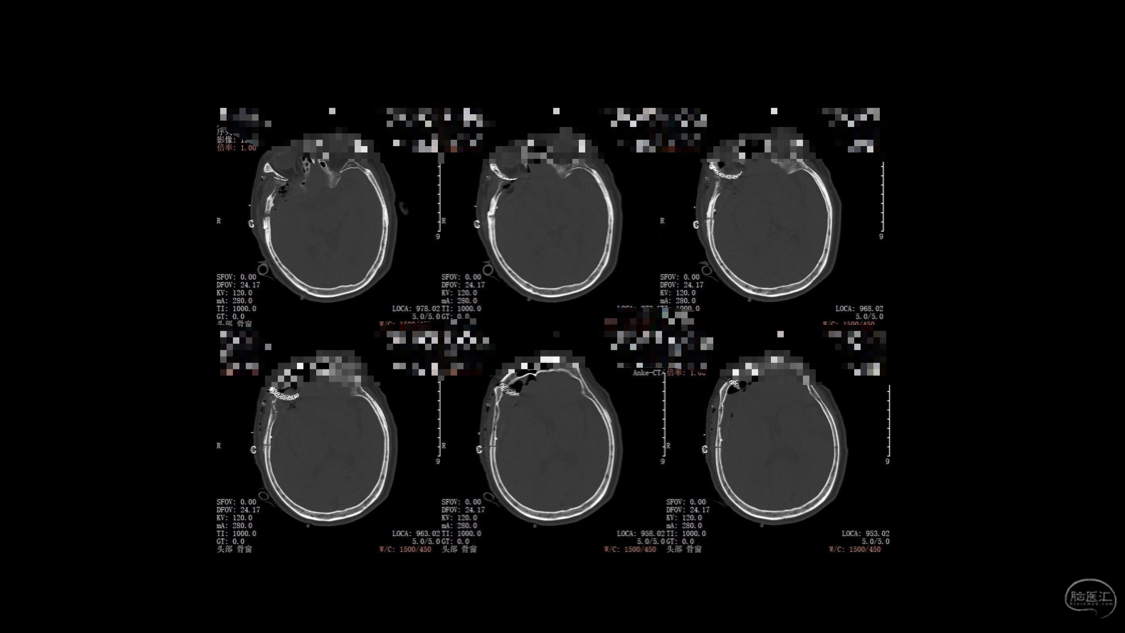

陈保东教授手术作品-右眶内及海绵窦旁孤立性纤维瘤